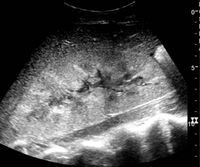

US is useful for diagnostic and prognostic purposes in chronic kidney disease. Whether the underlying pathologic change is glomerular sclerosis, tubular atrophy, interstitial fibrosis or inflammation, the result is often increased echogenicity of the cortex. The echogenicity of the kidney should be related to the echogenicity of either the liver or the spleen (Figure 22 and Figure 23). Moreover, decreased renal size and cortical thinning are also often seen and especially when disease progresses (Figure 24 and Figure 25). However, kidney size correlates to height, and short persons tend to have small kidneys; thus, kidney size as the only parameter is not reliable.[1]

Figure 25. End-stage chronic kidney disease with increased echogenicity, homogenous architecture without visible differentiation between parenchyma and renal sinus and reduced kidney size. Measurement of kidney length on the US image is illustrated by ‘+’ and a dashed line.[1]